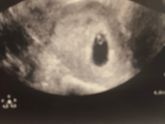

Сегодня было первое УЗИ, беременность маточная, есть плодное яйцо и сердцебиение ❤️